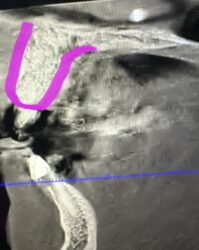

ANDREW started the discussion Infected #8, Pt wants implant in the forum Implant Tx Planning 2 years ago

How would you guys proceed with this case? I am assuming we will need to rebuild the facial wall entirely. Thought about using a titanium mesh membrane tacked down after scrubbing the remaining socket out and placing pt on antibiotics. Question is should we go ahead and graft or wait to heal before grafting and membrane placement?